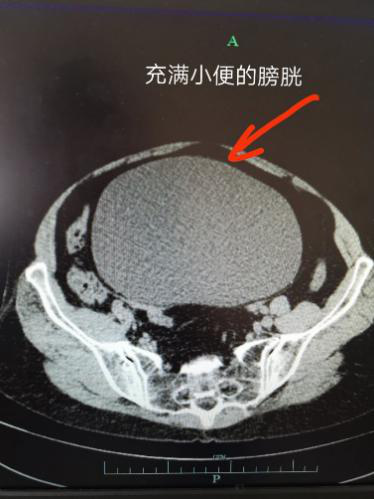

尿潴留:梗阻加重达到一定的程度,排尿时不能排尽膀胱内的全部尿液

尿潴留